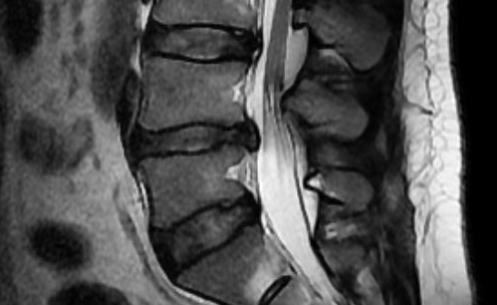

허리디스크는 의학용어로 ‘추간판탈출증’이라고 하는데요, 척추뼈(추체) 사이의 추간판이 제자리에서 벗어나 신경을 자극해서 통증이 발생하는 질환이에요.

추간판은 물렁한 연골 조직으로, 체중을 지탱하면서 움직임을 부드럽게 해주는 역할을 하거든요.

근데 평소 잘못된 자세나 외상으로 손상되면 추간판이 돌출되어 신경을 압박하게 돼요.

그 결과 허리는 물론이고 다리로 이어지는 다양한 통증이 나타날 수 있답니다.